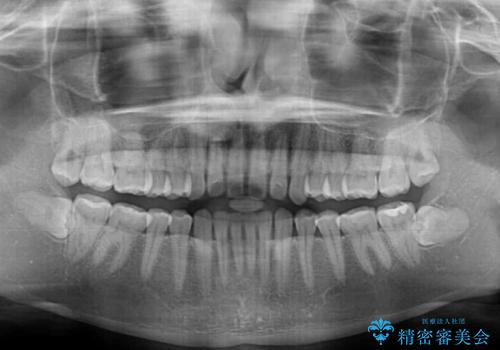

- 上顎前歯の隙間と口元の突出感を気にして来院された患者様です。

高校生の時に行った矯正治療の後戻りであり、歯列不正は軽度であったので、インビザラインにて治療を行うこととしました。